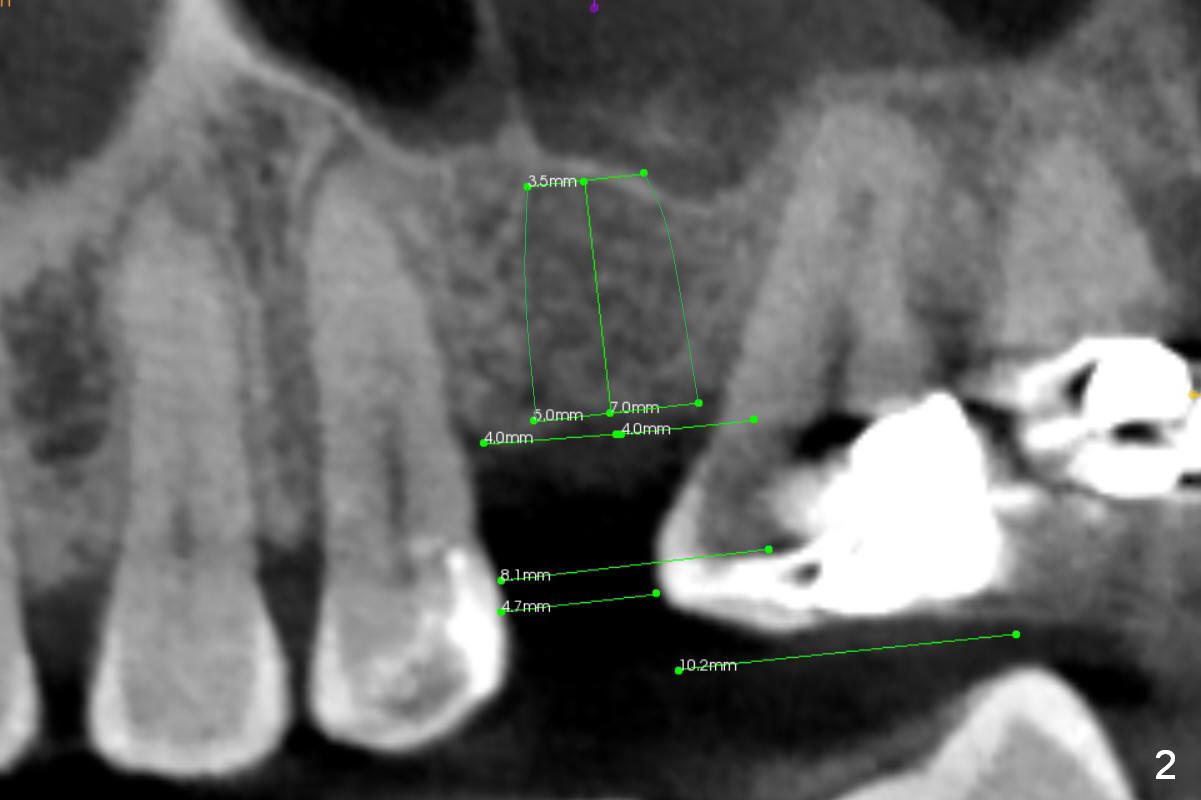

CT shows a residual root in the left maxillary sinus. In order not to re-infect the sinus, an implant at the site of #14 should not enter the sinus (Fig.2) or enters the sinus with bone graft (Fig.3,4 red circles) and more importantly PRF membrane (yellow).

Traditional segmental orthodontic treatment (open coil spring) is to be conducted to increase the mesiodistal width from 4.7 mm to 8 mm to place a 5 mm implant (Fig.2,3). Once the implant osteointegrates, it will be used an anchorage to further distalize the tooth #15.